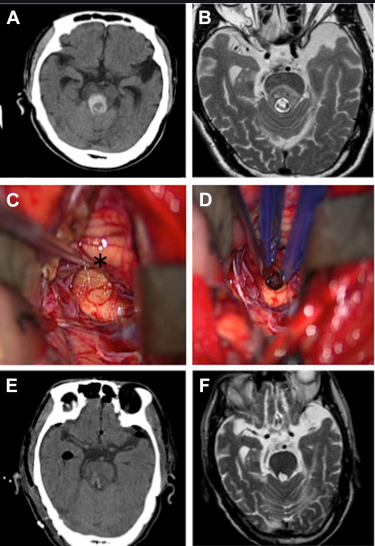

那么如何提高腦干海綿狀血管瘤生存期呢?前面也說了,想要提高生存期,擁有一個長的生命,及時治療是需的。而對于腦干海綿狀血管瘤的治療手術是主要手段,其中手術切除率的高低主要決定了治療效果,理想狀態(tài)下是全切,這樣才能確定不復發(fā)。目前手術主要包括傳統(tǒng)手術和顯微外科手術,但傳統(tǒng)手術切除率往往不能達到很理想的狀態(tài),因為憑借肉眼觀察,很多時候往往并不能清楚的看清腫瘤所在,達不到一個理想的切除率。而顯微外科手術借助于手術顯微鏡的放大,再結(jié)合神經(jīng)導航、術中MRI、術中超聲等輔助設備,視野更清晰、入路豐富,細致的顯微手術器械及縫合材料,讓血管瘤切除率達到更高,手術順利性更有保障,創(chuàng)傷面積更小,并且患者生存率都有所提高。

海綿狀血管瘤一般位置都不會固定的出現(xiàn)在同一個地方,每個人的腦海綿狀血管瘤位置都會有所差異。以往的手術治療入路單一,創(chuàng)傷面積大,而國際腫瘤顱底手術教授巴特朗菲教授擁有20年的腦干海綿狀血管瘤的外科治療經(jīng)驗,可以從多種入路更好的靠近多區(qū)域的腫瘤進行切除,減少患者術后的痛苦,減低感染的風險。術后,37%的患者表現(xiàn)出短暫的(輕微)神經(jīng)功能缺損,其余超過90%的患者,神經(jīng)功能與術前持平或好轉(zhuǎn)。

1.枕下后正中入路:可以到達腦部中后方,四腦室的底部以及延頸交界區(qū)域,比較適合位于腦干背側(cè)的腦干海綿狀血管瘤;

2.乙狀竇后入路:此入路可到達腦橋后面的外側(cè)部,小腦中腳(又稱腦橋臂)的外側(cè),以及延腦部的外上方區(qū)域,適合用于腦橋腹側(cè)以及腦橋腹外側(cè)的腦干海綿狀血管瘤;

3.幕下小腦上入路:通過幕下小腦上入路可以從頭部正中,偏中間以及頭側(cè)邊進行手術,適合用于松果體區(qū)的腦干海綿狀血管瘤;

4.眼顴入路:可到達中腦的前部和后側(cè)部分以及三腦室的后方,比較適合發(fā)生在中腦腹側(cè)和腹外側(cè)的腦干海綿狀血管瘤;

5.Kawase入路:能通過顳下膜外的入路到達巖骨尖部,通過磨除Kawase三角進入顱后窩,能夠好的暴露腦干復側(cè)進行腦干海綿狀血管瘤的切除;

6.翼點入路:可更好的達到中腦的前部,適合中腦腹側(cè)的腦干海綿狀血管瘤。

在巴特朗菲教授一份關于72名海綿狀血管瘤患者研究報告中顯示,在顯微外科手術后的72人中,大部分患者沒有再出血等其他不良癥狀,術后生活質(zhì)量得以明顯好轉(zhuǎn)。

參考文獻:Tsuji Y, Kar S, Bertalanffy H. Microsurgical Management of Midbrain Cavernous Malformations: Predictors of Outcome and Lesion Classification in 72 Patients[J]. Operative Neurosurgery, 2019.